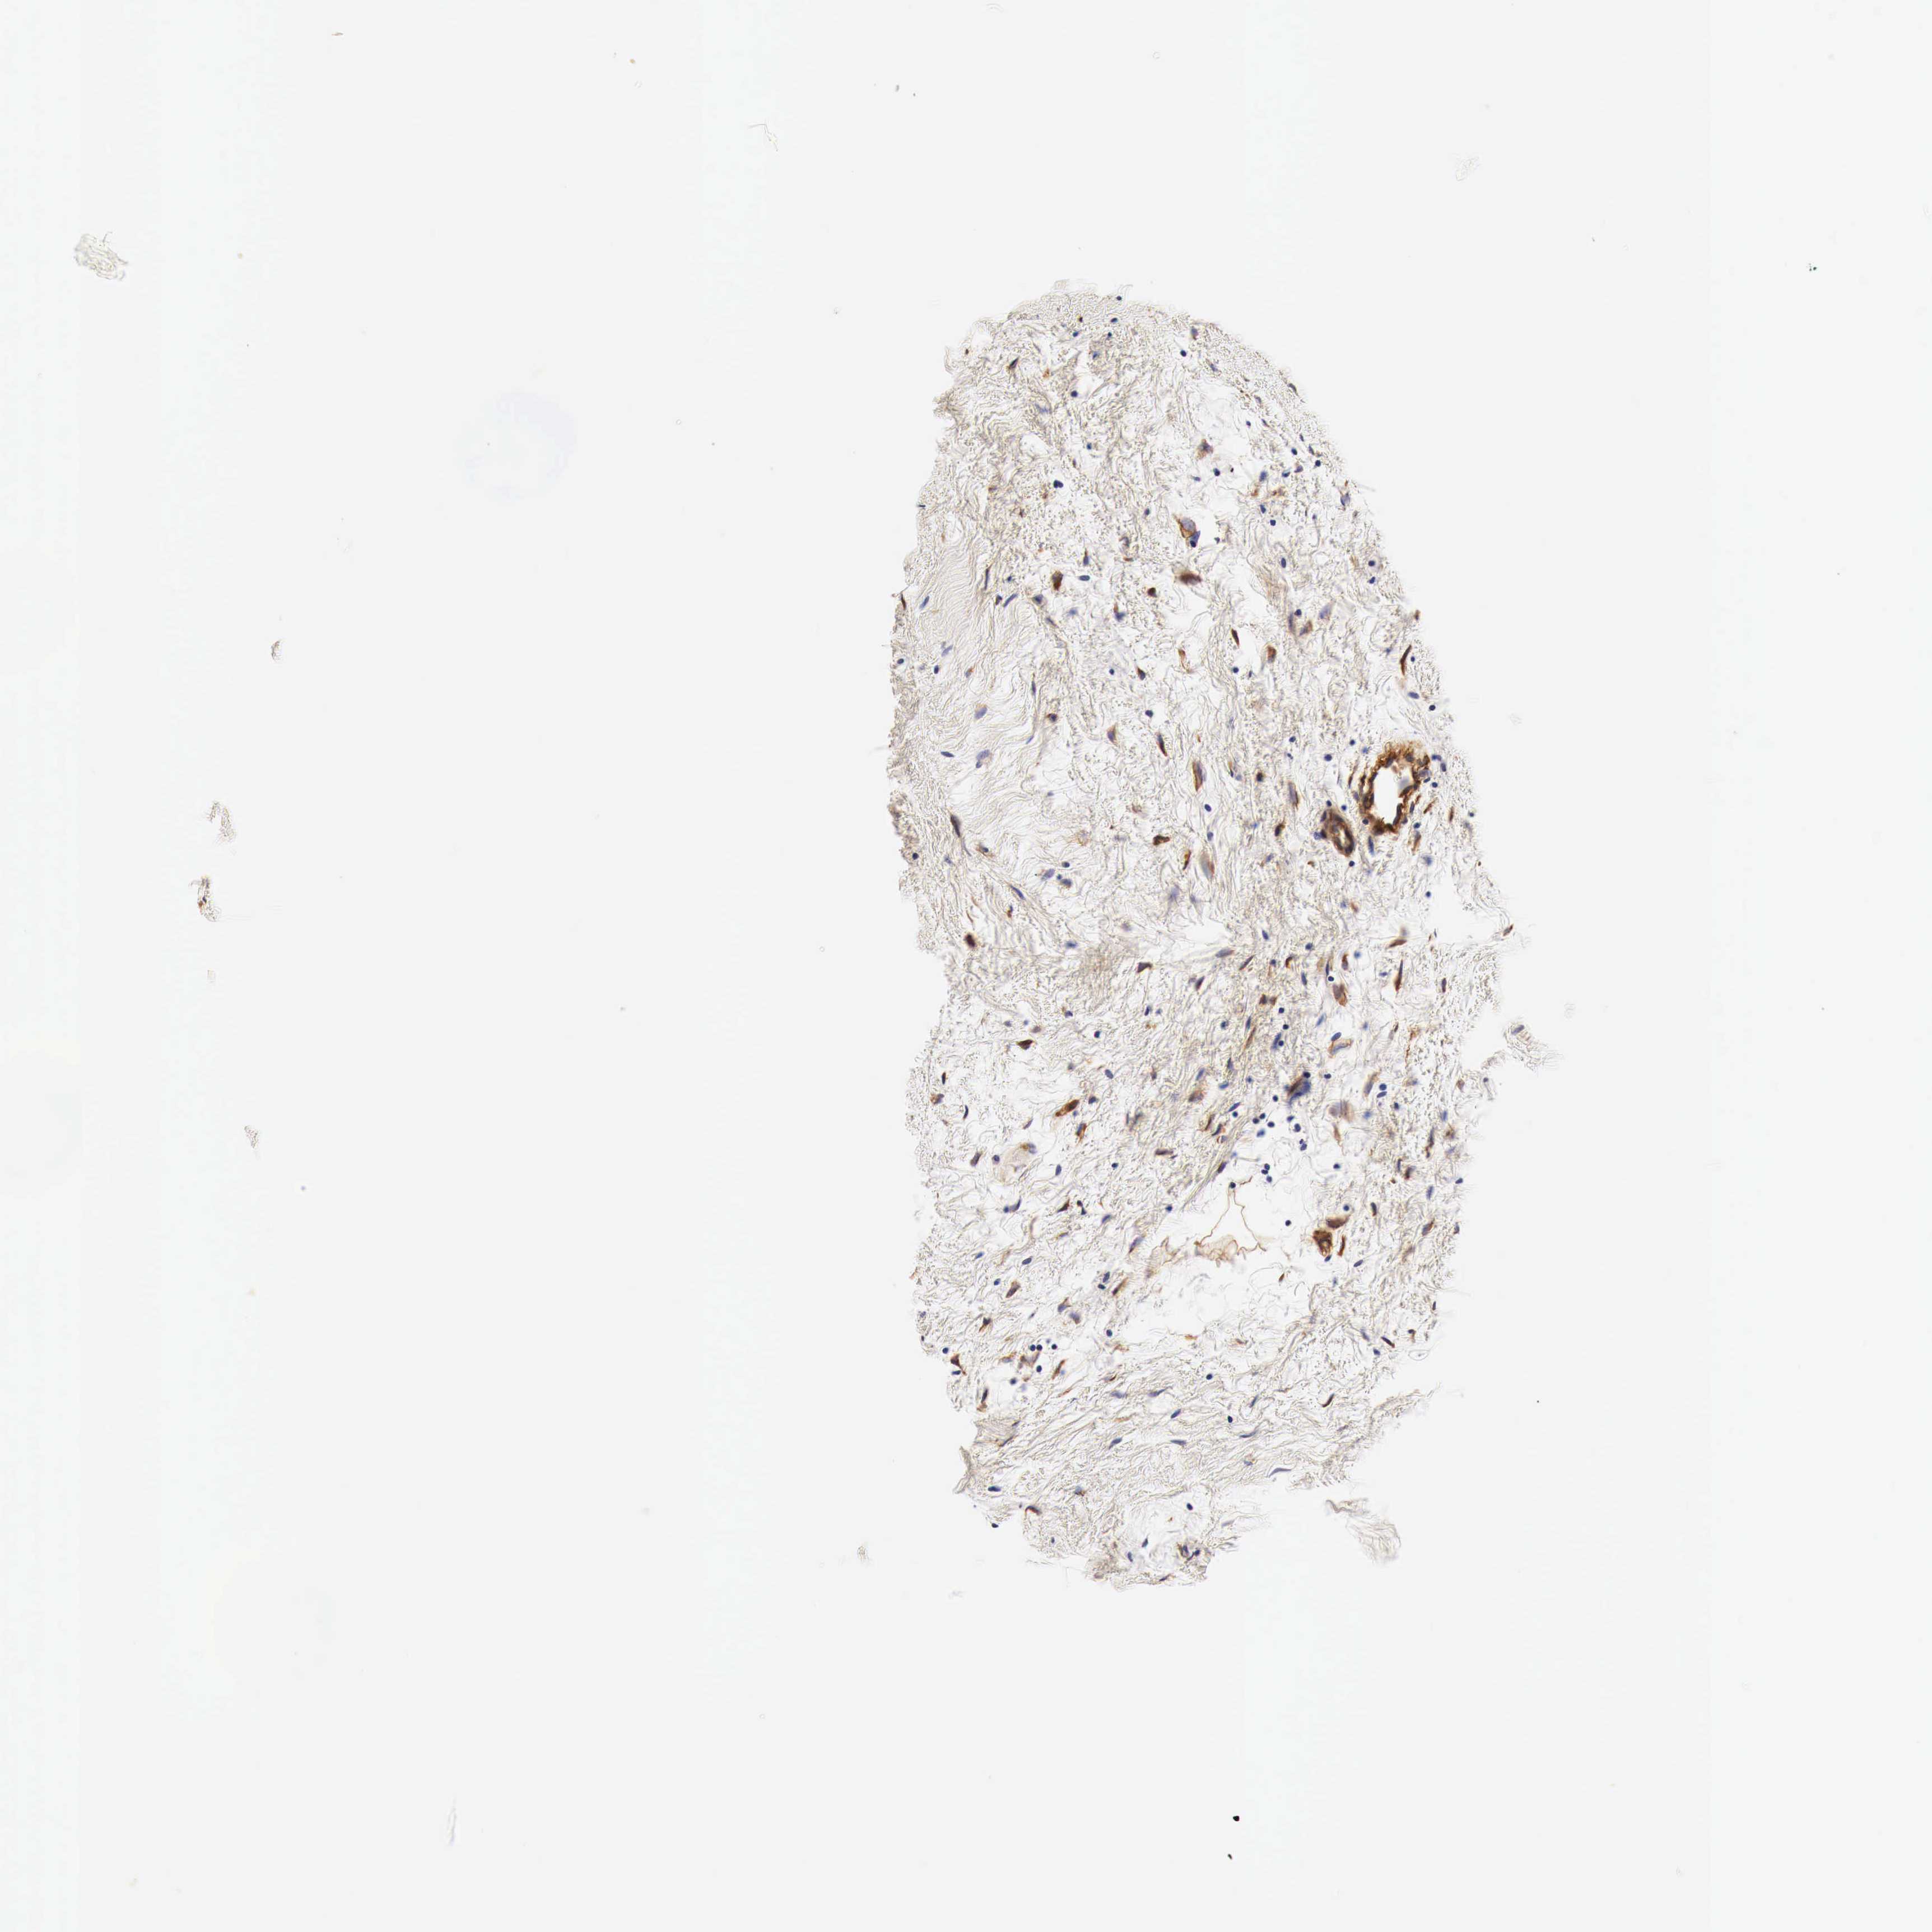

CANCER BREAST CANCER Show tissue menu

BRCA TCGA BRCA VALIDATION PROTEIN EXPRESSION

ANTIBODIES

AND

VALIDATION

Breast cancer

Human cancer